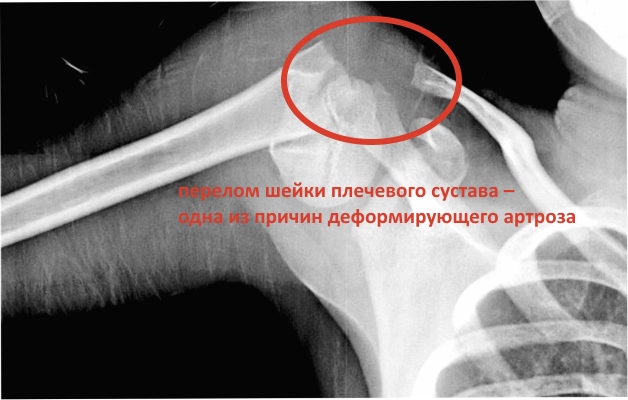

- травмы;

Основным профессиональным методом диагностики вышеописанного заболевания является рентгенография. Кроме нее или вместо нее врачи могут назначить МРТ, КТ, артроскопию.